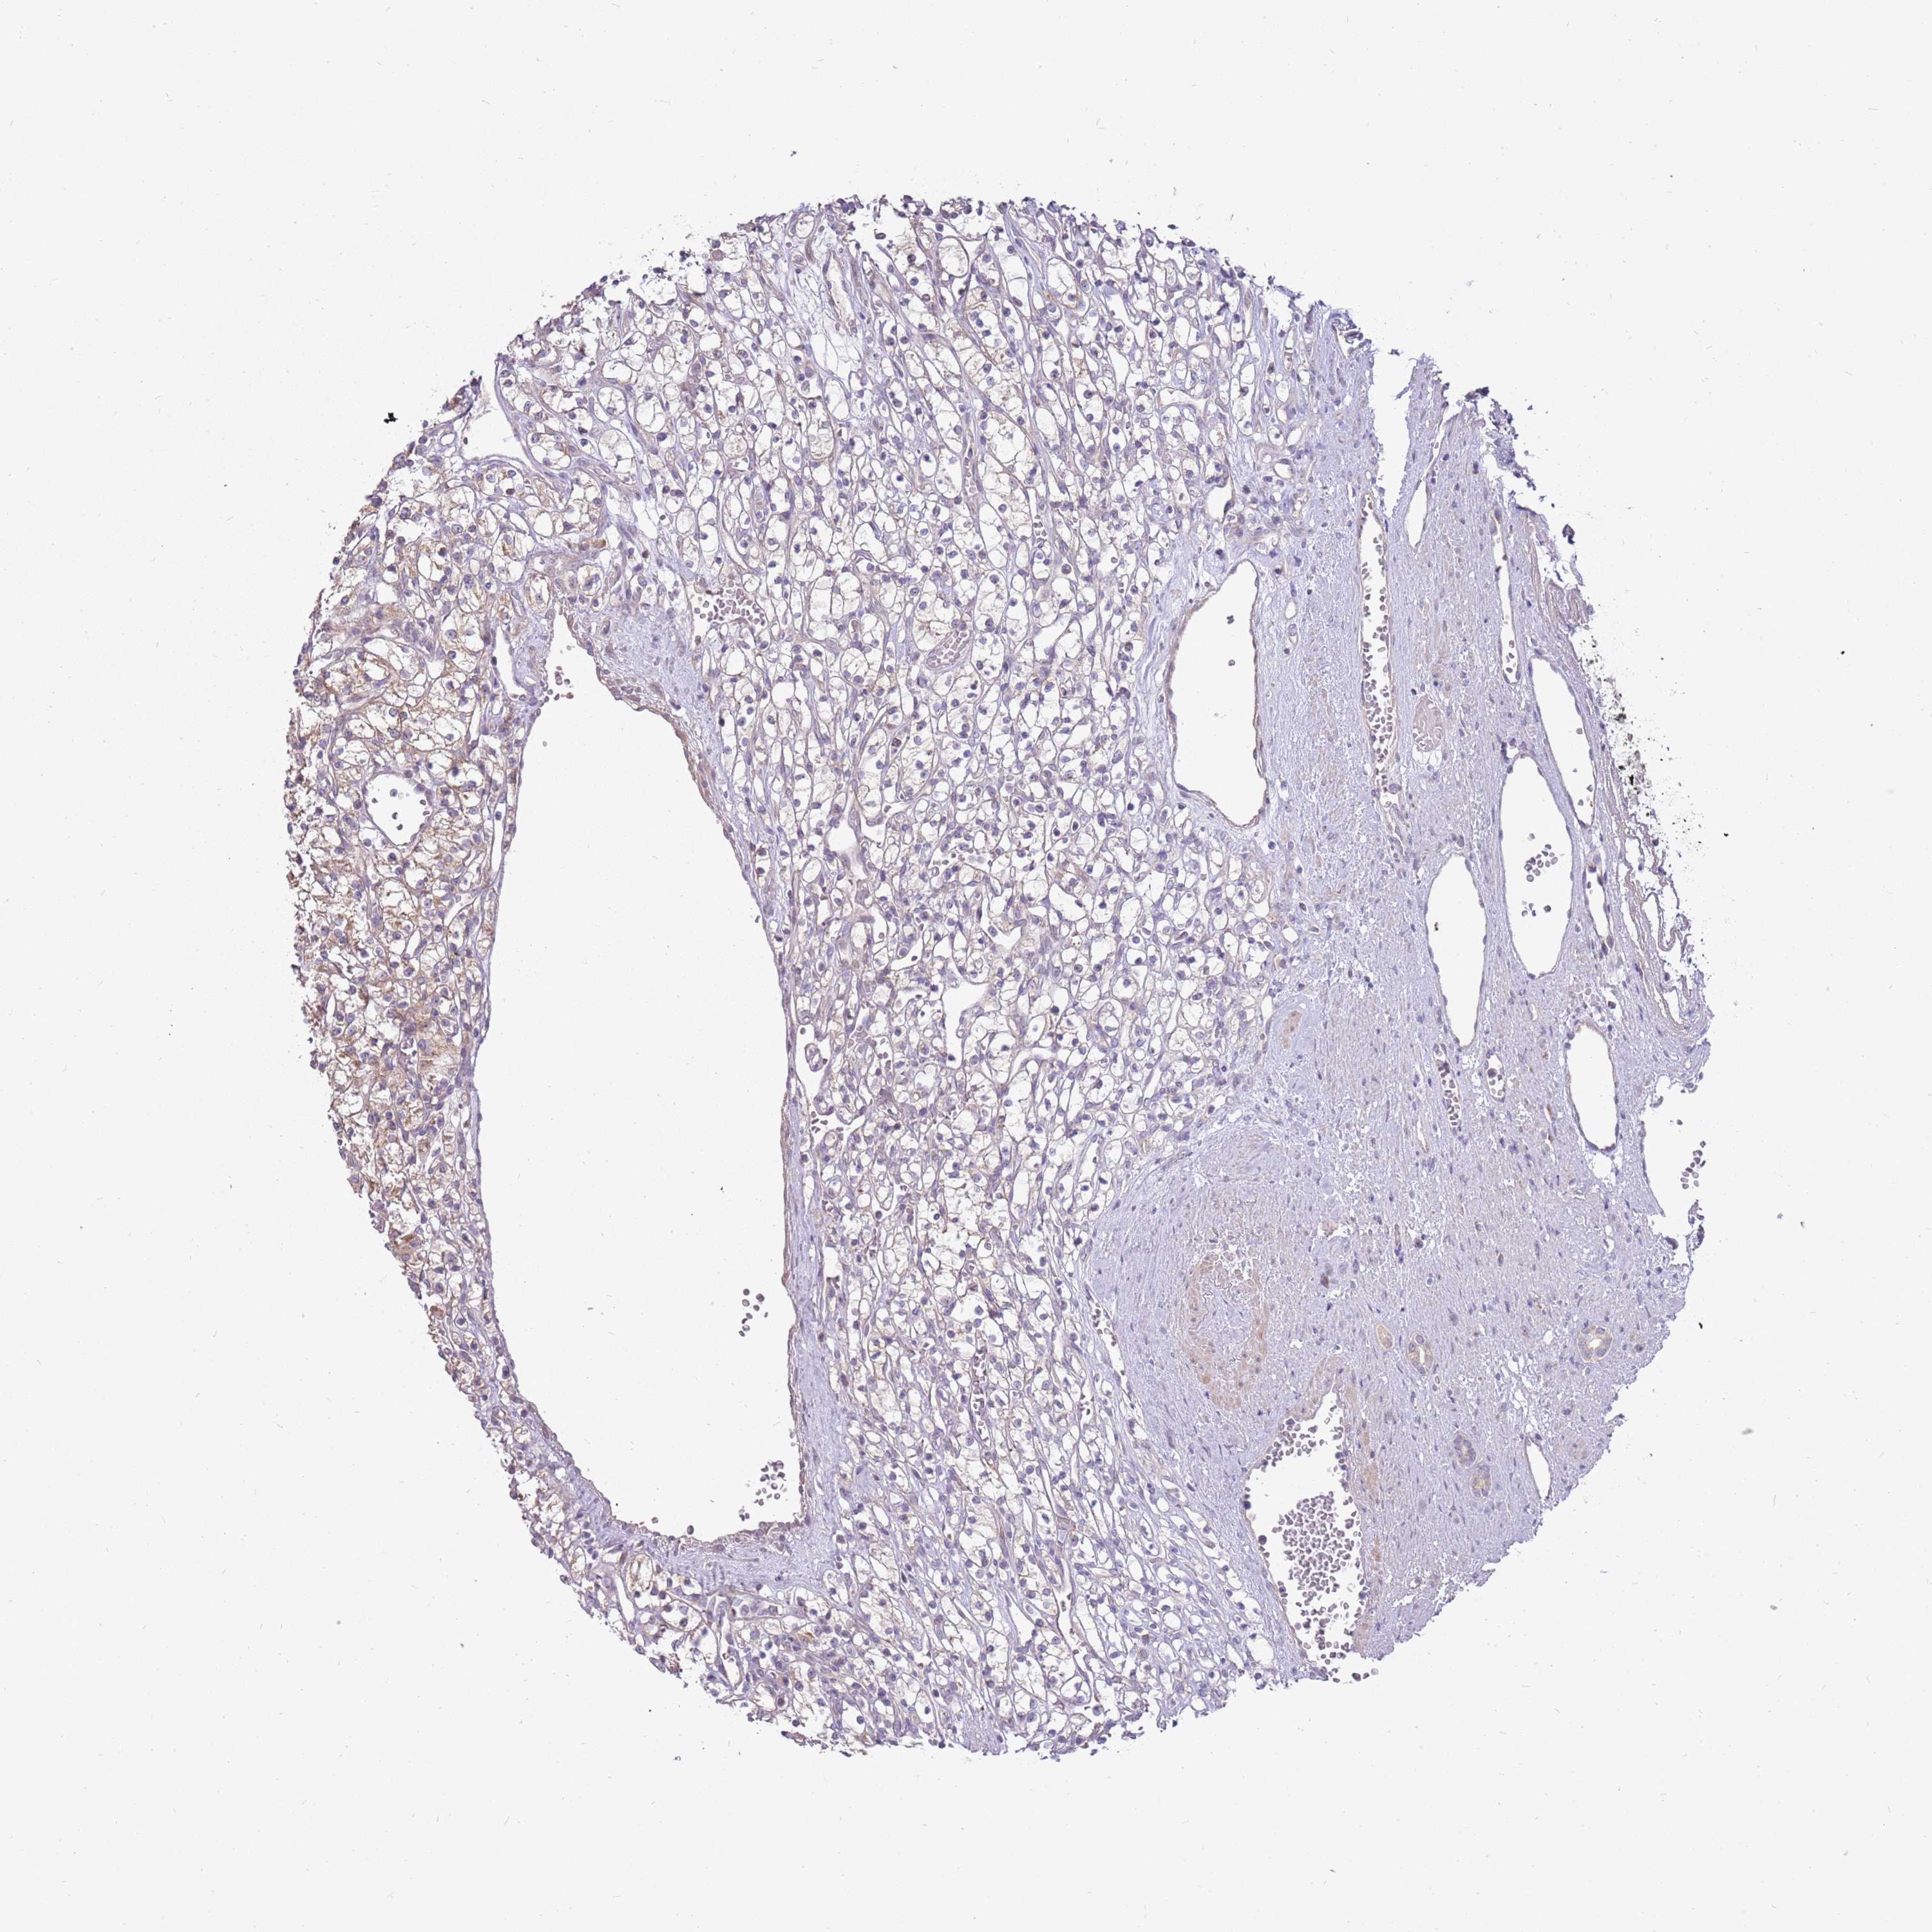

KIDNEY RENAL CLEAR CELL CARCINOMA (VALIDATION) - Interactive survival scatter ploti

The Survival Scatter plot shows the clinical status (i.e. dead or alive) for all individuals in the patient cohort, based on the same data that underlies the corresponding Kaplan-Meier plots. Patients that are alive at last time for follow-up are shown in blue and patients who have died during the study are shown in red.

The x-axis shows the expression levels (FPKM) of the investigated gene in the tumor tissue at the time of diagnosis. The y-axis shows the follow-up time after diagnosis (years). Both axes are complimented with kernel density curves demonstrating the data density over the axes. The top density plot shows the expression levels (FPKM) distribution among dead (red) and alive patients (blue). The right density plot shows the data density of the survived years of dead patients with high and low expression levels respectively, stratified using the cutoff indicated by the vertical dashed line through the Survival Scatter plot. This cutoff is automatically defined based on the FPKM cutoff that minimizes the p-score. The cutoff can be changed by dragging the vertical line or by entering a cutoff value in the square labeled "Current cut-off".

Under the Survival Scatter plot the p-score landscape (black curve; left axis) is shown together with dead median separation (red curve; right axis). Dead median separation is the difference in median mRNA expression between patients who have died with high and low expression, respectively. It is calculated as follows: median FPKM expression of dead patients with high expression - median FPKM expression of dead patients with low expression. This is intended to aid the user in visually exploring custom cutoffs and the associated p-scores and dead median separation.

Individual patient data is displayed and can be filtered by clicking on one or more of the category buttons on the top of the page. Categories describing expression level and patient information include: high, low, alive, dead, female, male and tumor stages. The scale of the x-axis can be toggled between linear and log-scale by clicking on the "x log" button. Mouse-over function shows TCGA ID, patient information and mRNA expression (FPKM) for each patient.

& Survival analysisi

Kaplan-Meier plots summarize results from analysis of correlation between mRNA expression level and patient survival. Patients were divided based on level of expression into one of the two groups "low" (under cut off) or "high" (over cut off). X-axis shows time for survival (years) and y-axis shows the probability of survival, where 1.0 corresponds to 100 percent.

LRFN3 is not prognostic in Kidney Renal Clear Cell Carcinoma (validation)

Best expression cut offi

Based on the FPKM value of each gene, patients were classified into two groups and association between prognosis (survival) and gene expression (FPKM) was examined. The best expression cut-off refers the FPKM value that yields maximal difference with regard to survival between the two groups at the lowest log-rank P-value. Best expression cut-off was selected based on survival analysis .

When clicking on this number, the vertical dashed line indicating cut-off, the interactive survival plot, and the Kaplan-Meier curve will be adjusted to show results based on the best expression cut-off.

: 2.88

P scorei

Log-rank P value for Kaplan-Meier plot showing results from analysis of correlation between mRNA expression level and patient survival.

N/A

TCGA RNA samplesi

RNA-seq data is reported as average FPKM (number Fragments Per Kilobase of exon per Million reads), generated by the The Cancer Genome Atlas (TCGA) .

Normal distribution across the dataset is visualized with box plots, shown as median and 25th and 75th percentiles. Points are displayed as outliers if they are above or below 1.5 times the interquartile range. FPKM values of the individual samples are presented next to the box plot.

Average pTPM 3.6

Number of samples 100